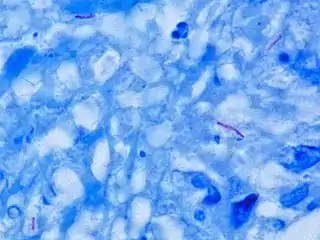

Mycobacterium tuberculosis (M. tb), also known as Koch's bacillus, is a species of pathogenic bacteria in the family Mycobacteriaceae and the causative agent of tuberculosis.[1][2] First discovered in 1882 by Robert Koch, M. tuberculosis has an unusual, waxy coating on its cell surface primarily due to the presence of mycolic acid. This coating makes the cells impervious to Gram staining, and as a result, M. tuberculosis can appear weakly Gram-positive.[3] Acid-fast stains such as Ziehl–Neelsen, or fluorescent stains such as auramine are used instead to identify M. tuberculosis with a microscope. The physiology of M. tuberculosis is highly aerobic and requires high levels of oxygen. Primarily a pathogen of the mammalian respiratory system, it infects the lungs. The most frequently used diagnostic methods for tuberculosis are the tuberculin skin test, acid-fast stain, culture, and polymerase chain reaction.[2][4]

Other bacteria are commonly identified with a microscope by staining them with Gram stain. However, the mycolic acid in the cell wall of M. tuberculosis does not absorb the stain. Instead, acid-fast stains such as Ziehl–Neelsen stain, or fluorescent stains such as auramine are used.[4] Cells are curved rod-shaped and are often seen wrapped together, due to the presence of fatty acids in the cell wall that stick together.[12] This appearance is referred to as cording, like strands of cord that make up a rope.[9] M. tuberculosis is characterized in tissue by caseating granulomas containing Langhans giant cells, which have a "horseshoe" pattern of nuclei.